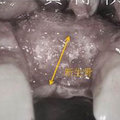

新生骨 瀏覽38 推薦0

骨粉 瀏覽40 推薦0